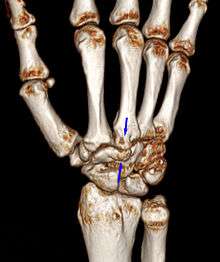

Carpal boss VR-3D-Reconstruction

Carpometacarpal bossing (or metacarpal/carpal bossing is a small, immovable mass of bone on the back of the wrist. The mass occurs in one of the joints between the carpus and metacarpus of the hand, called the carpometacarpal joints, where a small immovable protuberance[1] occurs when this joint becomes swollen or bossed.

The carpometacarpal joint is usually found at the base of the second and third metacarpal bones at the point where they meet the small bones of the wrist.[2]